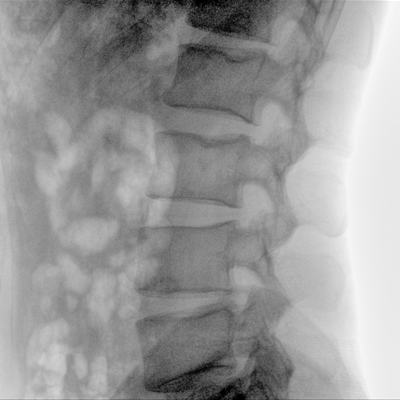

骨科: 經皮錐體成形術、經皮椎間盤臭氧治療術、胸脊椎固定、骨活檢、腰椎內固定術等。

優質平板探測器、可靈活升降調節SID、獨特圖像處理系統、高品質濾線柵,大視野成像清晰不失真。